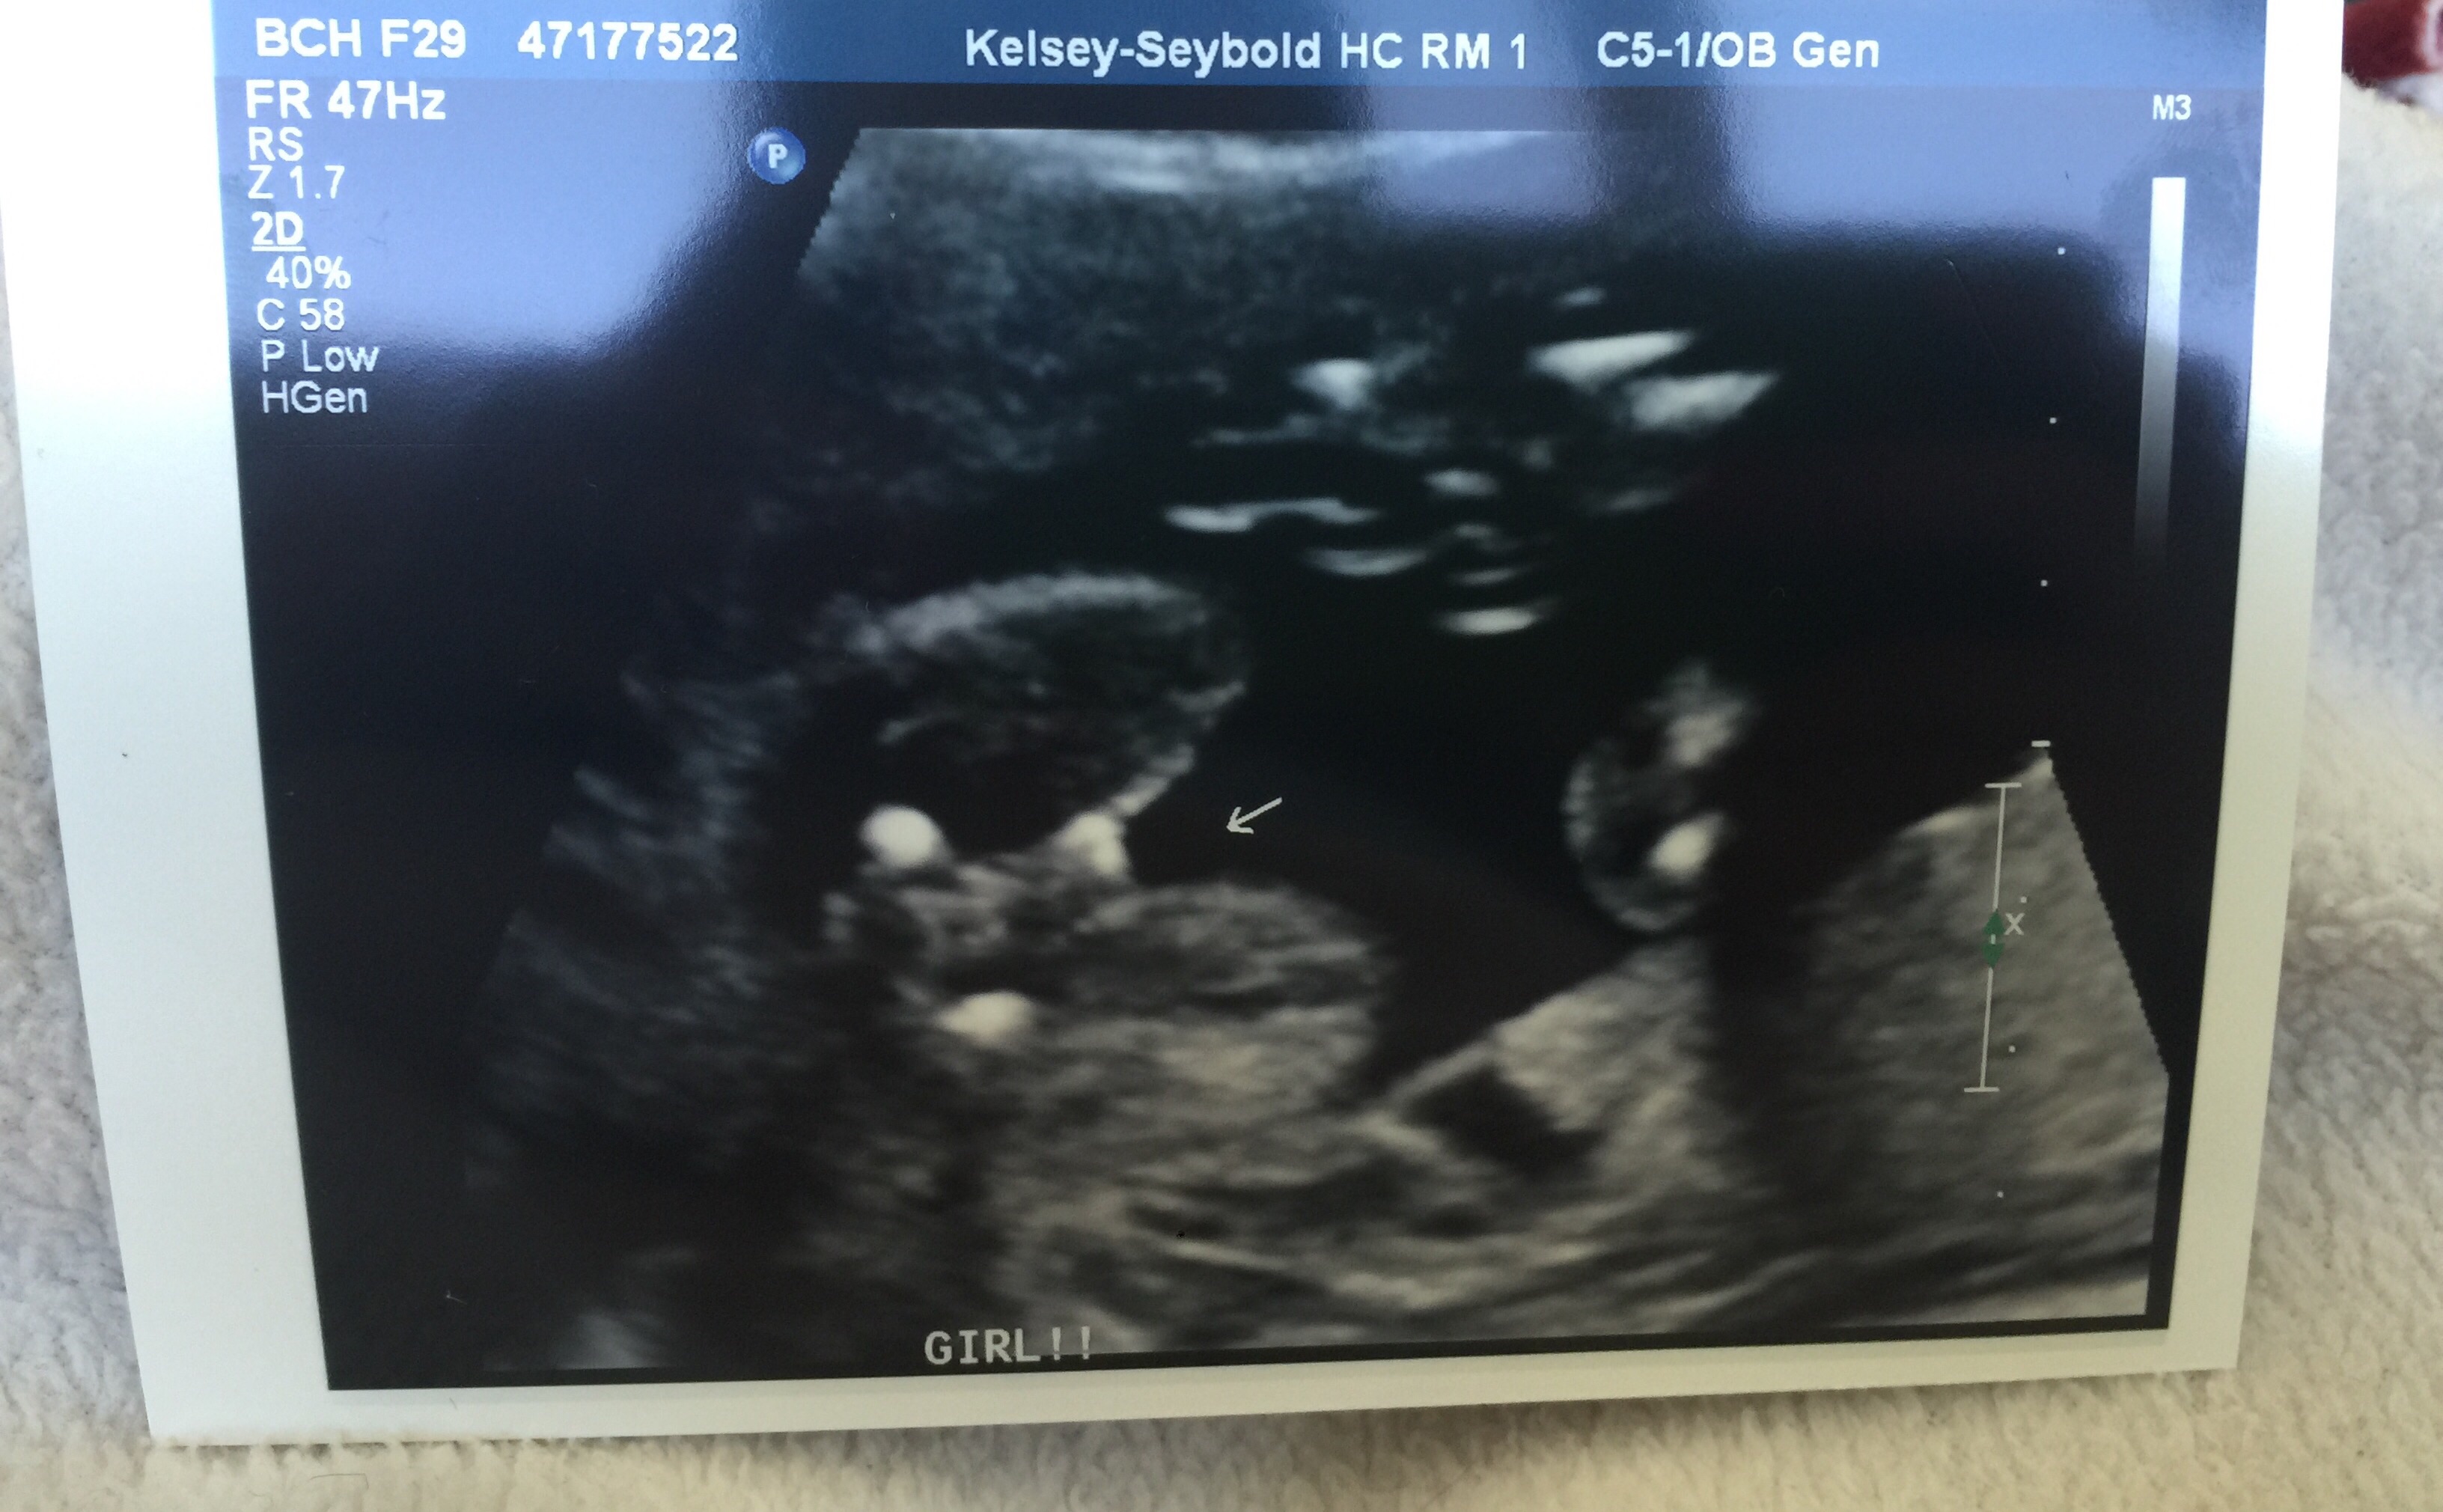

Had mine 7/9/15 @ 19 weeks exactly. My perinatologist was particularly looking for any heart defects and abnormalities in the kidneys or urinary tract--my little girl has a single umbilical artery (SUA; aka "two-vessel cord) and this abnormality has been correlated with abnormalities in these two organ systems. They did the fetal echo in conjunction with the anatomy scan and my perinatologist said everything looked great. This was my main concern so I feel as though a huge weight has been lifted. I was on the US table for over two hours so that she could get sonogram "video" of the heart and look at the kidneys more in depth too so it was definitely my longest US to date. We knew the sex was a girl from a prior 15w scan but it was confirmed again. She is measuring in the 33rd percentile, and we conceived 10 days after my last period, not 14, so she is actually likely a bit smaller. This is par for the course for SUA babies so my OB has already informed me we will be getting serial growth scans from here on out, Doppler velocimetry at each visit, as well as NST's weekly or twice weekly starting at 32 weeks (much earlier if she declines in growth percentile). SUA babies--mine LO's is "isolated", meaning it is not associated with a chromosomal abnormality or a organ defect--are at a significantly higher risk for IUGR and even stillbirth, thus the very close monitoring. If she drops below the 10th percentile in terms of growth it will be time to consider delivering via c-section since this would indicate she isn't getting the nutrients she needs due to the cord abnormality and would be "better out than in." My OB said he would likely not let her go past 37 weeks, so my little one could arrive closer to mid-November as opposed to closer to her due date of 12/3. Just seeing a beating 4-chambered heart that is structurally and functionally normal, two kidneys and a normal urinary tract just made my month. Literally.

We had our AS today and everything looked great! The tech said if she had seen something unusual she would have told the doctor and they would have talked to me but she said it looked great. She also confirmed it's a GIRL! We had a sneak peak last month and she just confirmed it (good thing because we already bought so many girl clothes while on vacation last week)! LO was all curled up in the bottom of my uterus and there was so much space up top... She was all cozy, moving around and then she got the hiccups! It was hard to get some of the shots thought because she was curled up so I had to go into all kinds of positions... Ouch! So worth it though!

We knew the sex was a girl from a prior 15w scan but it was confirmed again.